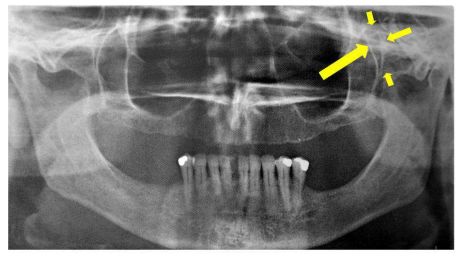

64.下圖黃色箭頭範圍內的解剖構造為下列何者? (A)zygomatic process (B)pterygomaxillary fissure (C)hamular process (D)infraorbital canal